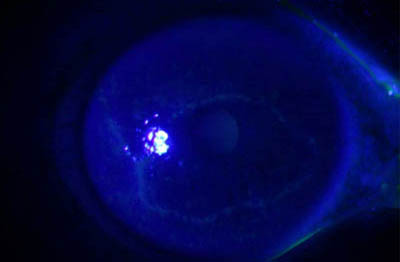

Perineuritis

No tienen los bulbos terminales de las dendritas del Herpes Simple

Formación de lineas epiteliales elevadas que pueden dar la imagen de Seudodendrítas

Formación de lineas epiteliales elevadas que pueden dar la imagen de Seudodendrítas

Formación de lineas epiteliales elevadas que pueden dar la imagen de Seudodendrítas + Perineuritis

Perineuritis